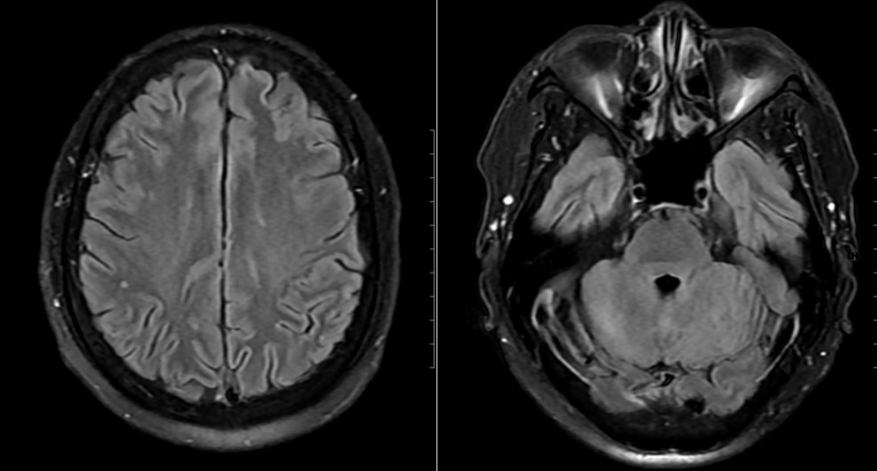

Mặc dù chưa có biểu hiện thần kinh rõ ràng, bệnh nhân vẫn được chọc dò dịch não tủy để loại trừ biến chứng. Kết quả cho thấy dịch não tủy tăng tế bào và protein, phản ứng Pandy dương tính, xác định tình trạng viêm não – màng não. Hình ảnh MRI sọ não còn phát hiện ổ tổn thương nhỏ tại thùy chẩm trái.

Từ các dữ liệu lâm sàng và cận lâm sàng, bệnh nhân được chẩn đoán mắc nhiễm khuẩn huyết – viêm não màng não do Streptococcus suis. Ngay khi nhập viện, người bệnh được điều trị kháng sinh đường tĩnh mạch và hiệu chỉnh theo kháng sinh đồ, đồng thời theo dõi sát tình trạng toàn thân và thần kinh.

Sau 24 giờ, bệnh nhân cắt sốt, thể trạng cải thiện rõ. Sau 15 ngày điều trị tích cực, các xét nghiệm và hình ảnh học cho thấy tổn thương hồi phục hoàn toàn, bệnh nhân xuất viện trong tình trạng ổn định, không để lại di chứng thần kinh.